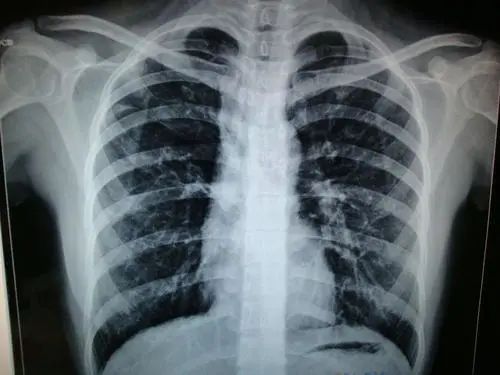

#肺钙化灶

肺钙化灶一般是由肺部炎症引起,最常见的原因是肺结核。其次,气管支气管炎、肺炎、肺癌、甲状旁腺功能亢进、钙或磷酸盐代谢异常、血栓以及气管支气管淀粉样变、纤维化也可诱发肺钙化灶生成。

一般来说肺钙化灶在正常人中也是比较常见的,可能是由于炎症愈合后留下的,这种情况是不需要治疗的。但是考虑到部分患者有吸烟史,可能会发展为肺癌。建议去医院做一个专业的检查,同时嘱咐要戒烟、清淡饮食。